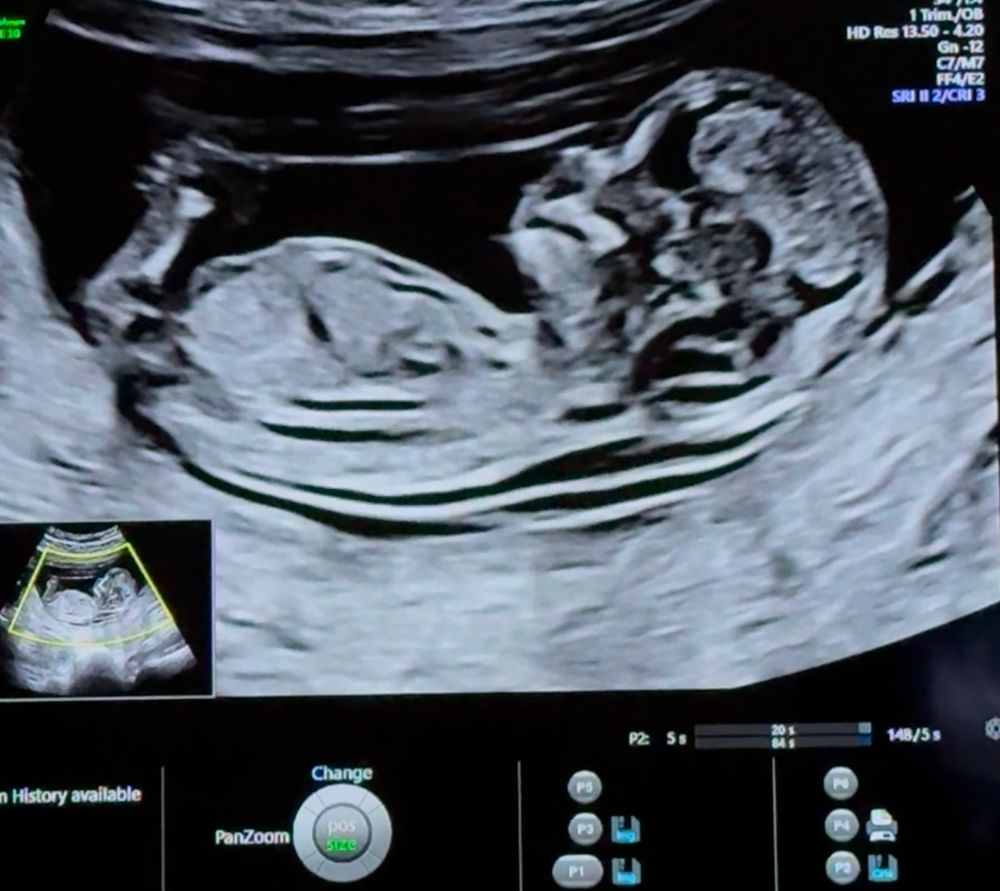

Пол ребенка в 12 недель (половой бугорок), мальчик или девочка?

за ножкой не видно бугорка(

У меня сын на первом скрининге прям писюн показал😃. Думаю девочка.

Так не видно же.

Вроде как на девочку похоже, у мальчиков бугорок "крючёчком" вверх

Сбоку ножкой закрылся, а снизу на таком сроке не смотрят ☺️